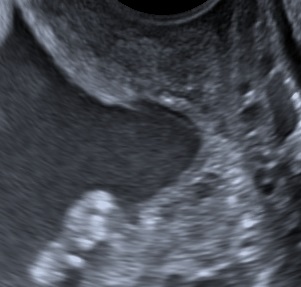

- Median sagittal view of the cervix.

- Calipers between the triangular area of echodensity at the external os and the V-shaped notch at the internal os.

- Examination-time 2-3 minutes (shortest measurement).